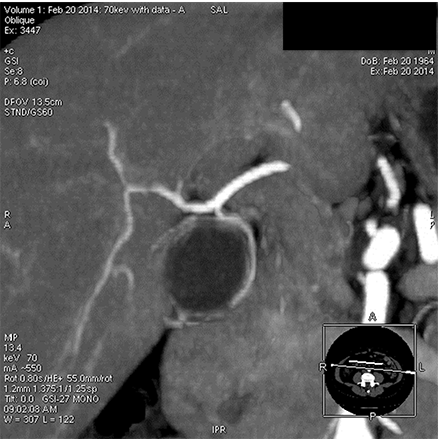

能谱 低keV图像血管成像

胆囊供血动脉   50keV

胆囊动脉及其分支发育细小,常规CTA难以完整显示,即使提高造影剂浓度、总量及注射流率也无法来满微小动脉显示的需求,受扫描时相影响较大。

GSI扫描能使用低keV 图像满足空间分辨率和密度分辨率兼顾的要求,在常规造影剂注射方案情况下,一次扫描通过调整keV同时满足诊断及微小动脉显示需要。该方法可在临床解剖研究、病变血供发现、血管受侵状况、手术指导等方面有重要作用。